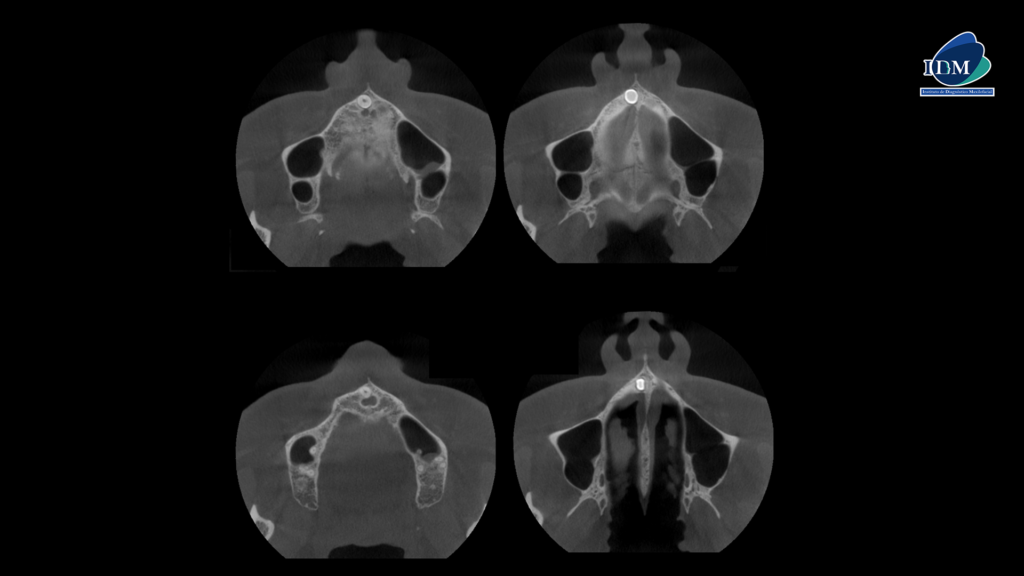

Así mismo en la tomografía volumétrica de haz se evidencia que dicha pieza está ubicada en zona vestibular. Contactando con el conducto nasopalatino, próximo a ápice de la pieza 11 y con el segmento coronario contactando con piso de fosa nasal derecho.

CORTES AXIALES